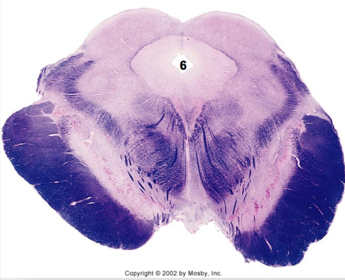

| Spinal tract of V | |

| Spinal nucleus of V | |

| Medial vestibular nucleus | |

| Inferior vestibular nucleus | |

| Dorsal cochlear nucleus | |

| Ventral cochlear nucleus | |

| Inferior olivary complex | |

| Inferior cerebellar peduncle | |

| CN IX | |

| Anterior spinocerebellar tract | |

| Central tegmental tract | |

| Olivary internal arcuate fibers | |

| Solitary tract | |

| Abducens root fibers | |

| Longitudinal pontine fibers (corticospinal tract) | |

| Transverse pontine fibers (dark fibers) | |

| Pontine nuclei (pale) | |

| Medial lemniscus | |

| ALS | |

| Trapezoid body | |

| Ventral trigeminothalamic tract | |

| Superior olive | |